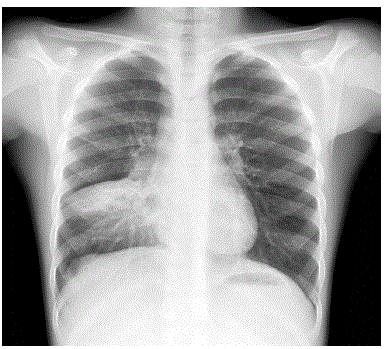

ATENÇÃO: O caso seguinte se refere às questões 90 e 91:

Lactente masculino, 2 meses de idade, nascido de termo, parto vaginal, sem intercorrências até o momento, está sendo reavaliado na retaguarda de um Pronto-Socorro. Há 4 dias iniciou quadro de coriza hialina e tosse, e há um dia evoluiu com desconforto respiratório. Apresentou febre de até 38,6°C apenas no primeiro dia de história do quadro atual. O paciente deu entrada há cerca de 10 horas e está com a seguinte prescrição: Peso 4,8 kg

No momento da sua reavaliação, o paciente está em regular estado geral, hidratado, pálido, com ausculta pulmonar com sibilos e crepitações difusas, tiragens subdiafragmática, intercostal e de fúrcula, batimento de asas nasais, FR: 88 ipm, saturação de oxigênio 90% com oferta de O2, FC: 180bpm, PA: 78/40mmHg. Sem alterações das propedêuticas cardíaca e abdominal. Tempo de enchimento capilar de 2 segundos, pulsos normais, sem edema.

Radiografia de tórax realizada há 15 minutos:

enunciado 1543319-2

Com relação ao suporte hídrico prescrito, está correto afirmar que: